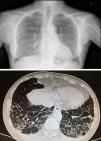

Radiografía y TAC de tórax. Distorsión del intersticio pulmonar a nivel subpleural de ambas bases, con engrosamiento del intersticio intralobulillar y septos interlobulillares, compatibles con fibrosis pulmonar predominante a nivel subpleural posterobasal. También bronquiectasias cilíndricas basales bilaterales.

Ingresó en julio de 2013 por brote purpúrico en miembros inferiores, debilidad, fiebre de 37,8°C, tos irritativa, náuseas y vómitos biliosos, junto con pérdida ponderal de hasta 10kg de peso en 2 meses. A la exploración resaltaba la púrpura cutánea y la hipoventilación bibasal, atribuida a su fibrosis pulmonar. Se confirmósu estabilidad en un TACAR de control (fig. 1), sin adenopatías palpables. Analíticamente destacaba anemia aguda normocítica normocrómica, no hemolítica ni ferropénica, con proteinograma normal (9g/dl Hb), creatinina 1,07mg/dl (aclaramiento 68ml/min), proteinuria 200mg/dl (0,38g/24h) y sedimento 20 H/C (56% dismorfias). Autoinmunidad habitual positiva (ANA+,Ro+,La+,hipocomplementemia C4 1mg/dl,IgM y FR muy elevados). Además de, en la actualidad, hipocomplementemia C3 66mg/dl, descenso de IgG 600mg/dl (previamente normal) y crioglobulinas positivas. Serología para hepatitis C,B y para VIH, negativa. ANCA negativos. Se realizó biopsia de piel informada como vasculitis leucocitoclástica de pequeño vaso. La biopsia renal de 28 glomérulos fue la que sigue: glomerulomegalia,esclerosis global en 3 glomérulos y, en los restantes, lesiones de isquemia-plegamiento de membrana basal, hipercelularidad mesangial y endocapilar, y ocasionales pequeños trombos hialinos PAS+con células inflamatorias en su interior CD68+;infiltrado intersticial mononuclear, fibrosis leve y atrofia, inflamación e isquemia tubular focal;arteriolas con depósito focal de sustancia hialina PAS+y engrosamiento intimal en una inmunofluorescencia (9 glomérulos/1 esclerosado); IgM+en focos de células inflamatorias intersticiales y alrededor de túbulos;C3±heterogéneo mesangial y en paredes vasculares;hibridación in situ Epstein-Barr negativa (fig. 2).